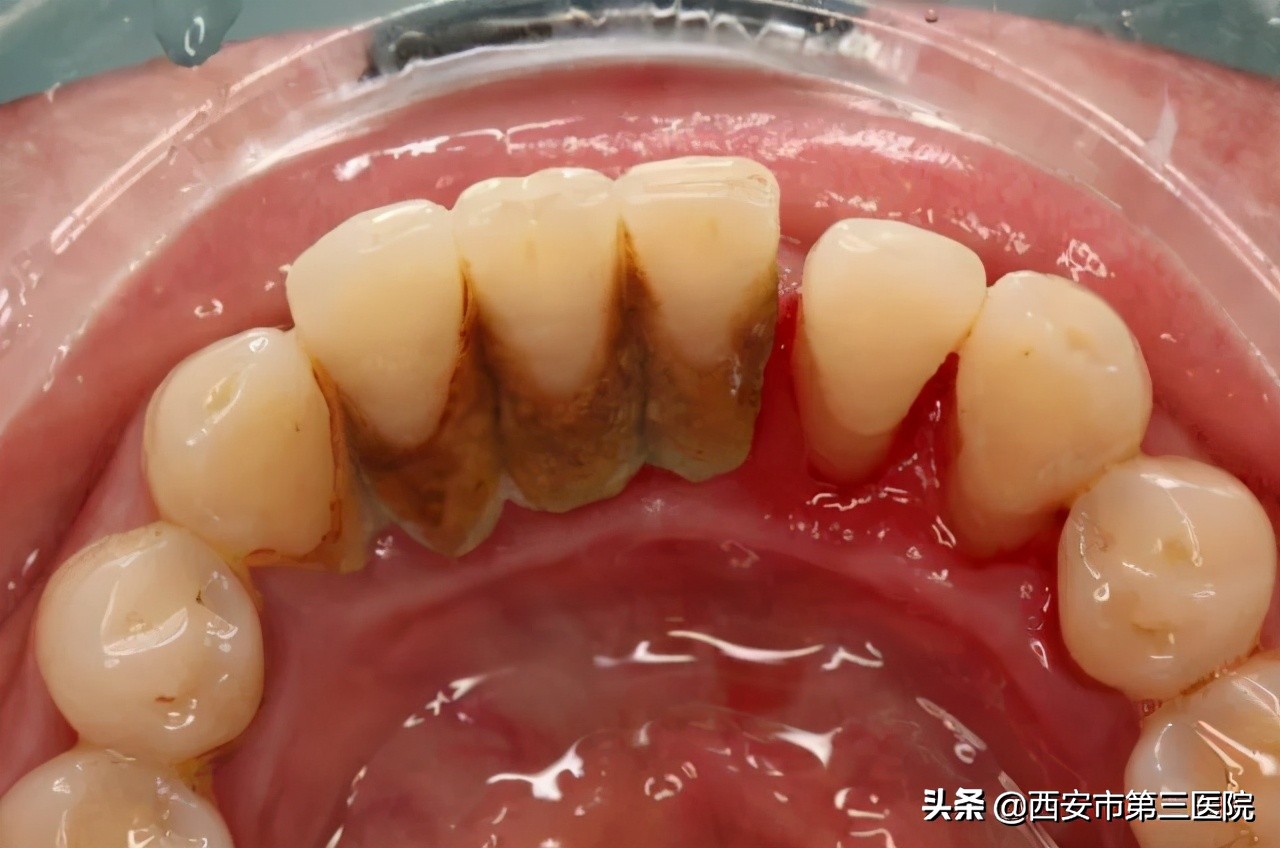

刷牙,只能清除牙齿和舌苔表面的食物残渣菌斑。但是,就算刷牙刷得特别好,总也阻止不了有些牙菌斑躲在隐蔽的角落,钙化变成牙结石。更别提,我们大多数人基本刷不好牙,也几乎不用牙线。所以,从没洗过牙的人,或多或少有牙结石。有牙结石,就得去洗牙了。

一旦牙结石达到相当程度,将不可避免地刺激牙龈发炎,牙龈出血,最终由牙龈炎不可逆地转变为牙周炎。牙周炎如果控制不当发展到中晚期时,牙龈会持续处于炎症状态,反复红肿发炎。其次,牙龈萎缩和牙槽骨丧失导致牙根暴露,牙齿松动移位,严重时牙齿自动脱落,丧失咀嚼功能。